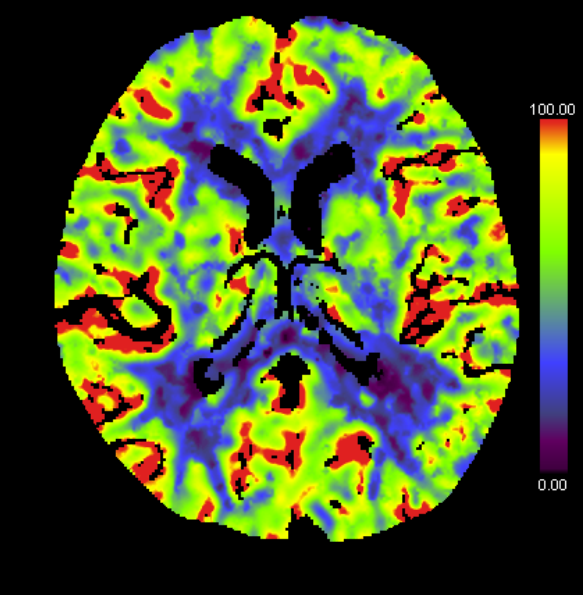

MRI 検査(磁気共鳴画像)

MRI 検査とは

MRI (Magnetic Resonance Image:磁気共鳴画像)とは、強力な磁場と電波を使って、体の中の水や脂肪など(人体の約 60 %は水分)を画像化する検査です。さまざまな角度から体の断面を撮像することが出来ますが、磁場なので CT とは違い X 線を使用しないため放射線被ばくはありません。

当院では 2013 年に MRI 棟が完成し、新しく 3.0T MRI を導入し、従来の 1.5T MRI と合わせて2台で稼働しております。3.0T MRI では、ワイドボア化となり、撮像空間を広く確保することができ、従来のものより圧迫感が緩和されました。さらに、磁場強度(磁石の力)が2倍となったため、より高画質になり微細構造まで見えるようになりました。